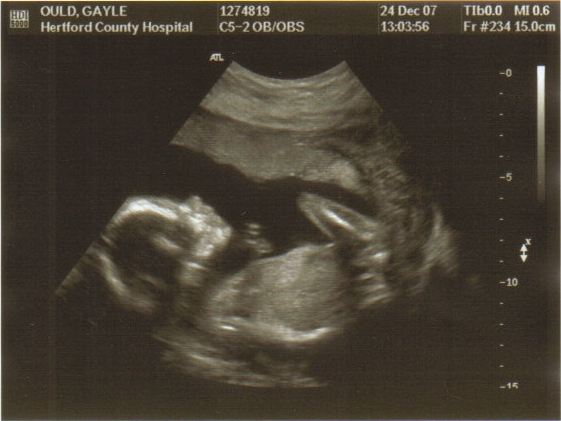

Yup, it’s the same child peeps. What’s the difference? On the left hand side he was 20 weeks old, able to feel pain, heart pumping, responding to external stimuli and completely dependable on his mother for food and nurture. The only difference on the right hand side was that he was 20 weeks older and that Gayle can’t now murder him if she just isn’t arsed to look after him.